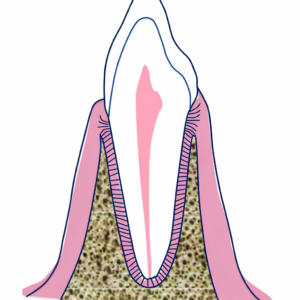

装置を外した直後の歯の周りの組織(歯槽骨や歯周組織)は、柔らかい状態にあります。歯を支える組織(歯根膜)はゴムのような弾性があり、約1年~2年をかけて作り替えられ、新しい位置に馴染んでいきます。

↑ 歯と骨の間にある繊維が歯周靭帯、歯根膜と呼ばれるものになります

この馴染むまでの間に何もしないと、歯は元のガタガタだった位置に戻ろうとします。これを後戻り(relapse)と呼びます。この歯周組織の作り替えが行われている間、きちんと戻らないように押さえておく必要があります。